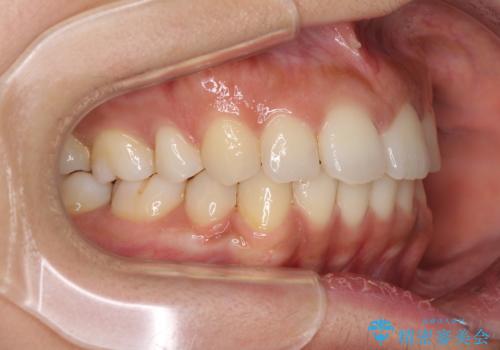

抜歯矯正の後戻り インビザラインによる再矯正治療

- 以前矯正治療をされていましたが、後戻りが起きたことを気にして来院された患者様です。

全顎的に認められた叢生を改善するため、インビザラインにて治療を行うこととしました。

前歯の叢生の改善を目的として、IPR(歯と歯の間を削る)と歯列全体の後方移動によって歯並びを整えることとしました。

毎日22時間の装着時間を守ってくださいましたが、ハイペースにマウスピースを交換することなく、慎重に治療を進めてくださったので、治療期間はやや長くなりました。

臼歯部も含め、叢生が綺麗に改善され、患者様には大変満足していただきました。